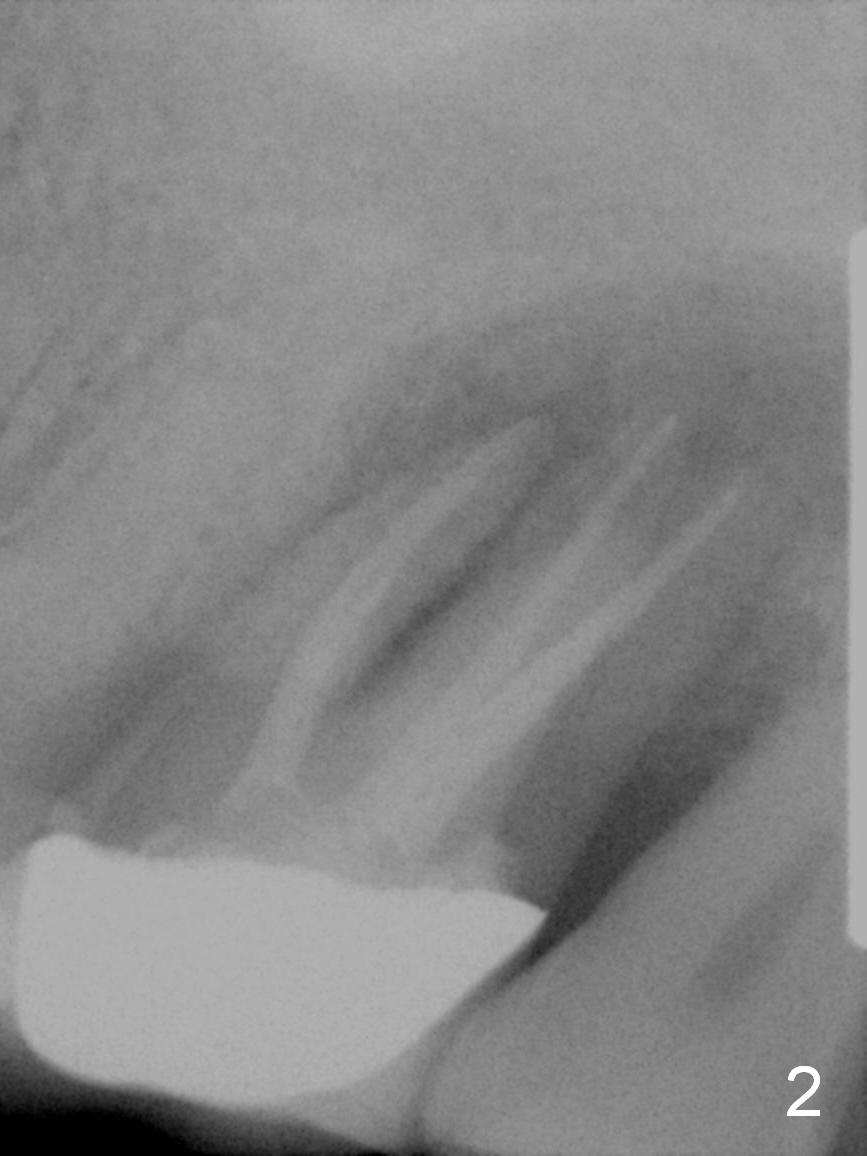

A 56-year-old woman has had sign of root fracture at the site of 15 for the last 3 years (Fig.2,3), 5 years after RCT (Fig.1). It appears that the sinus floor is around 1 mm and consists of the cortical bone (Fig.2). After extraction and Clindamycin disinfection, IBS Sinus Lifter (2 3) will be used, followed by allograft placement, 4.3 mm long drill, and 5x9 mm dummy implant. Take PA and measure depths relative to the sinus floor and crest. Prepare latch and hand implant drivers as well as calibrated torque wrench. Amalgam and large bone carriers should be available. Although primary stability is expected to be low, an immediate provisional should be fabricated with sufficient occlusal clearance. Since the bone density is high, use higher voltage to take X-ray.